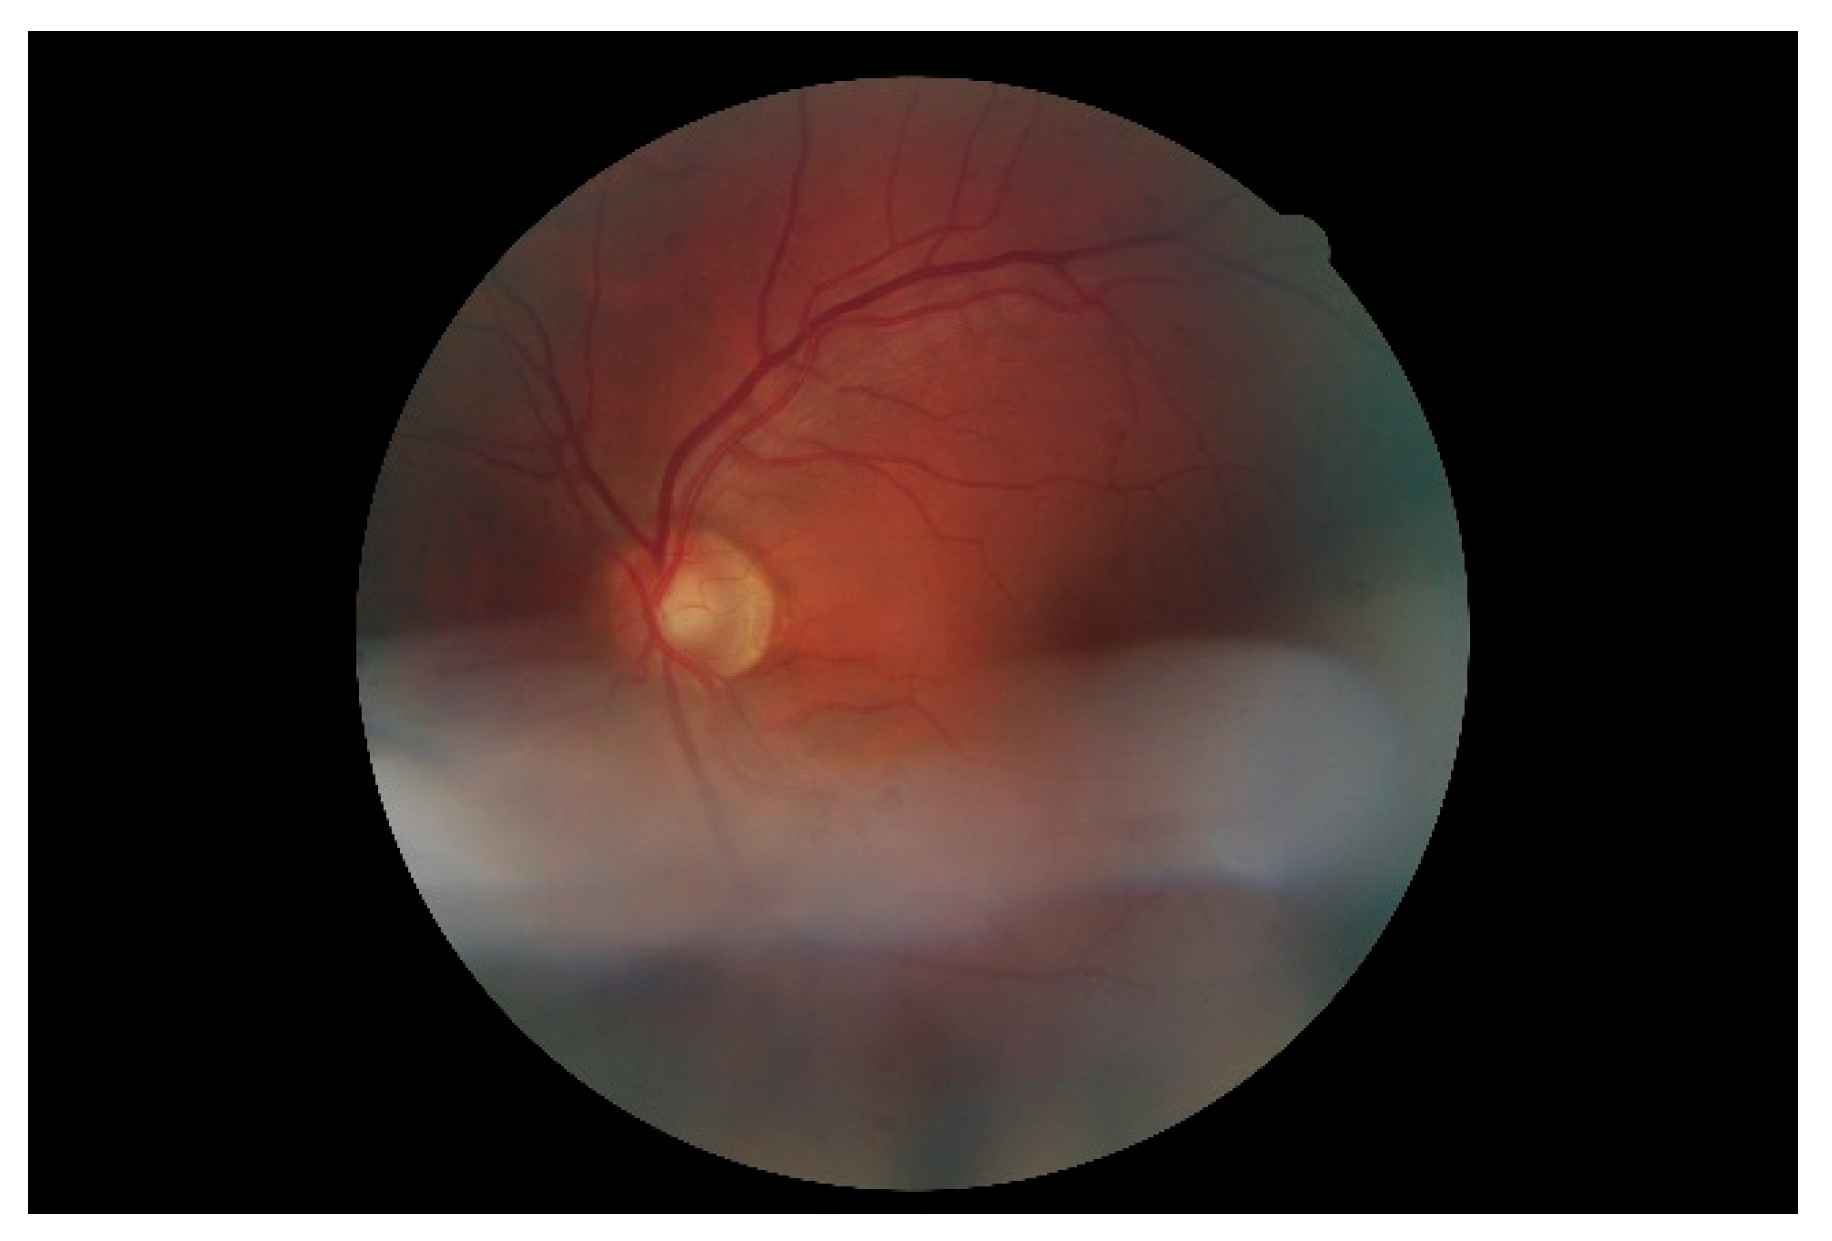

Figure 2. Example of a retinal image in digital retinal images for vessel extraction (DRIVE).

Retina images are digital images of the interior of the eye, specifically the rear portion. Retina images are required to show the retina, optic disk, and blood vessels, as shown in Figure 2. Figure 2 shows a retina image from the digital retinal images for vessel extraction (DRIVE) [59] dataset, which is often used in retina-related studies.

The techniques that are often used for automating retinal vessel segmentation are based on machine learning [28,29,30,31,32,33,34,35,36,37,38,39,40,41,42,43,44,45,46]. This is because replacing the lost vessel portion of an original retina image with another person’s vessels lacks ethical credibility. On the other hand, machine learning is credible because it learns patterns in which people’s vessels are spread. The focus of most recent studies is on deep learning-based supervised learning, and this is the same for retinal vessel segmentation automation. To learn vessel images, masks must be prepared in advance for the vessel portion. Figure 4 shows the manually prepared vessel portion of Figure 2. Moreover, the areas of the vessels must be specified when the dataset’s retina images are in a different environment (minor changes in position that occur when the image is captured). Figure 5 shows the position mask for Figure 2.